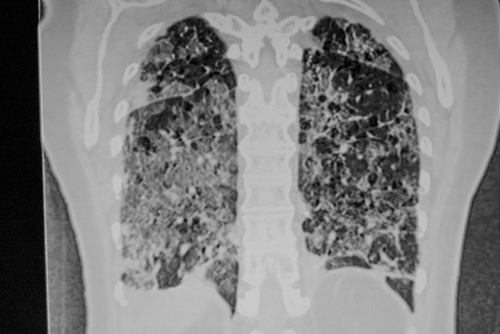

A la première consultation, 56 patients (soit 65 % des patients pris en compte dans cette analyse) voyaient la persistance d’au moins un symptôme de la Covid-19, le plus souvent de la dyspnée (40 patients, 47 %) ou de la toux (13 patients, 15 %), tandis que la tomodensitométrie montrait la persistance de lésions pulmonaires avec aspect de verre dépoli chez 88 % des patients (avec un score moyen de 8) et un VEMS abaissé à moins de 80 % de la normale chez 23 % des patients, la CVF étant également <80 % de la normale chez 24 patients (28 %) et la DLCO<80 % de la normale chez 28 patients (33 %).Il n’y avait par ailleurs pas de rapport entre la présence de lésions pulmonaires et la perturbation des tests fonctionnels ou avec les symptômes. Enfin, l’échocardiogramme montrait également chez 56 % des patients une dysfonction ventriculaire gauche. La biologie indiquait de son côté une atteinte cardiaque, thrombotique et inflammatoire.

Ces symptômes avaient heureusement tendance à s’améliorer comme en témoignent la persistance d’une dyspnée chez 31 patients (39 %). La toux était en revanche toujours présente chez les 13 patients qui en souffraient à 6 semaines. Quant à la tomodensitométrie, elle a montré une réduction du nombre de patients présentant des lésions en verre dépoli (dont le score moyen était passé à 4) soit 48 patients (56 %), tandis qu’un VEMS<80 % de la normale n’était plus observé que chez 18 patients (21 %), une CVF<80 % chez 16 patients (19 %) et une DLCO<80 % chez 19 patients (22 %). La biologie avait, chez tous, tendance à se normaliser.